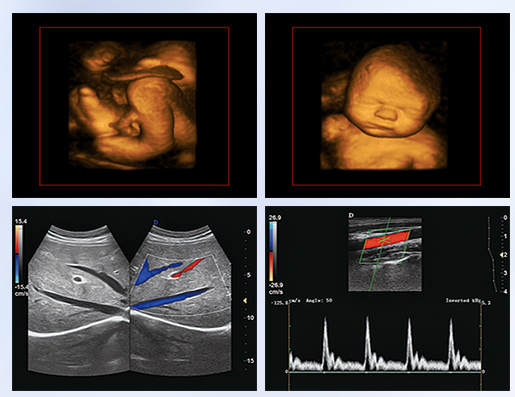

超聲學科的發(fā)展史,猶如一卷悠遠綿長的畫冊。從黑白B超機到彩超機,從一維、二維向三維立體動態(tài),從推車式B超機到便攜式彩超機,從觀察人體解剖學到分析人體組織內(nèi)細微結(jié)構(gòu)和功能。隨著科學技術(shù)的不斷發(fā)展,B超機功能也越來越方便強大。

超聲作為一門醫(yī)、理、工相結(jié)合的學科,涵蓋超聲診斷、超聲治療和超聲工程技術(shù)等門類,其在臨床診斷和治療中發(fā)揮著日益重要的作用。B超機借助各種超聲探頭,以精湛的技術(shù)和嚴謹?shù)膽B(tài)度掃描著人體臟器內(nèi)的細微病變,給臨床提供準確而快捷的檢查報告,在影影綽綽間,發(fā)現(xiàn)病魔的蛛絲馬跡中,用“金睛火眼”挽救患者性命……超聲的每一幅圖像,都是靠超聲醫(yī)生親自探查并采集的,每一個患者,至少都有10張以上的圖像存儲,對于比較復雜的病例,有幾十甚至上百張。而且所有的圖像,都需要超聲醫(yī)生在邊探查的時候,邊思考分析。這,是一個真正手腦并用的工作。